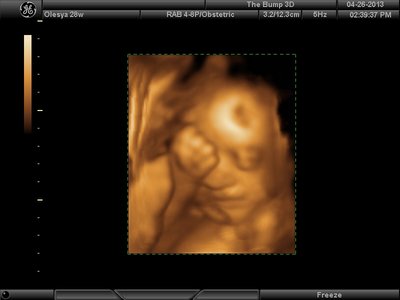

Еще одна, качество ужасное..

| Вложения: |

image.jpg [ 60.32 КБ | Просмотров: 1455 ]